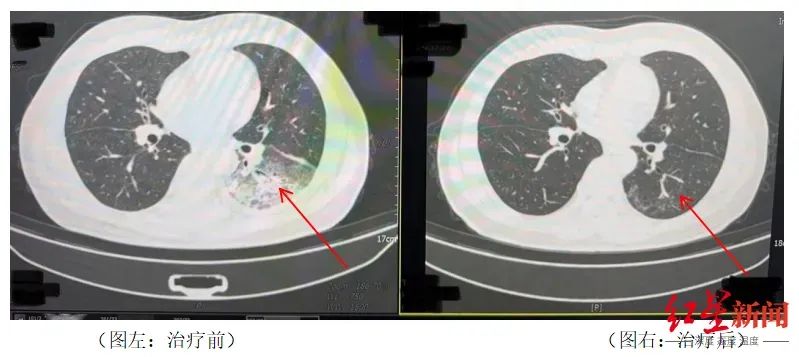

家人见状,立即将他送医。胸部CT显示李先生的左肺已出现大面积白色影像,几乎占据一半肺部。经过检测,最终确认是嗜肺军团菌肺炎

李先生肺部治疗前与治疗后的对比